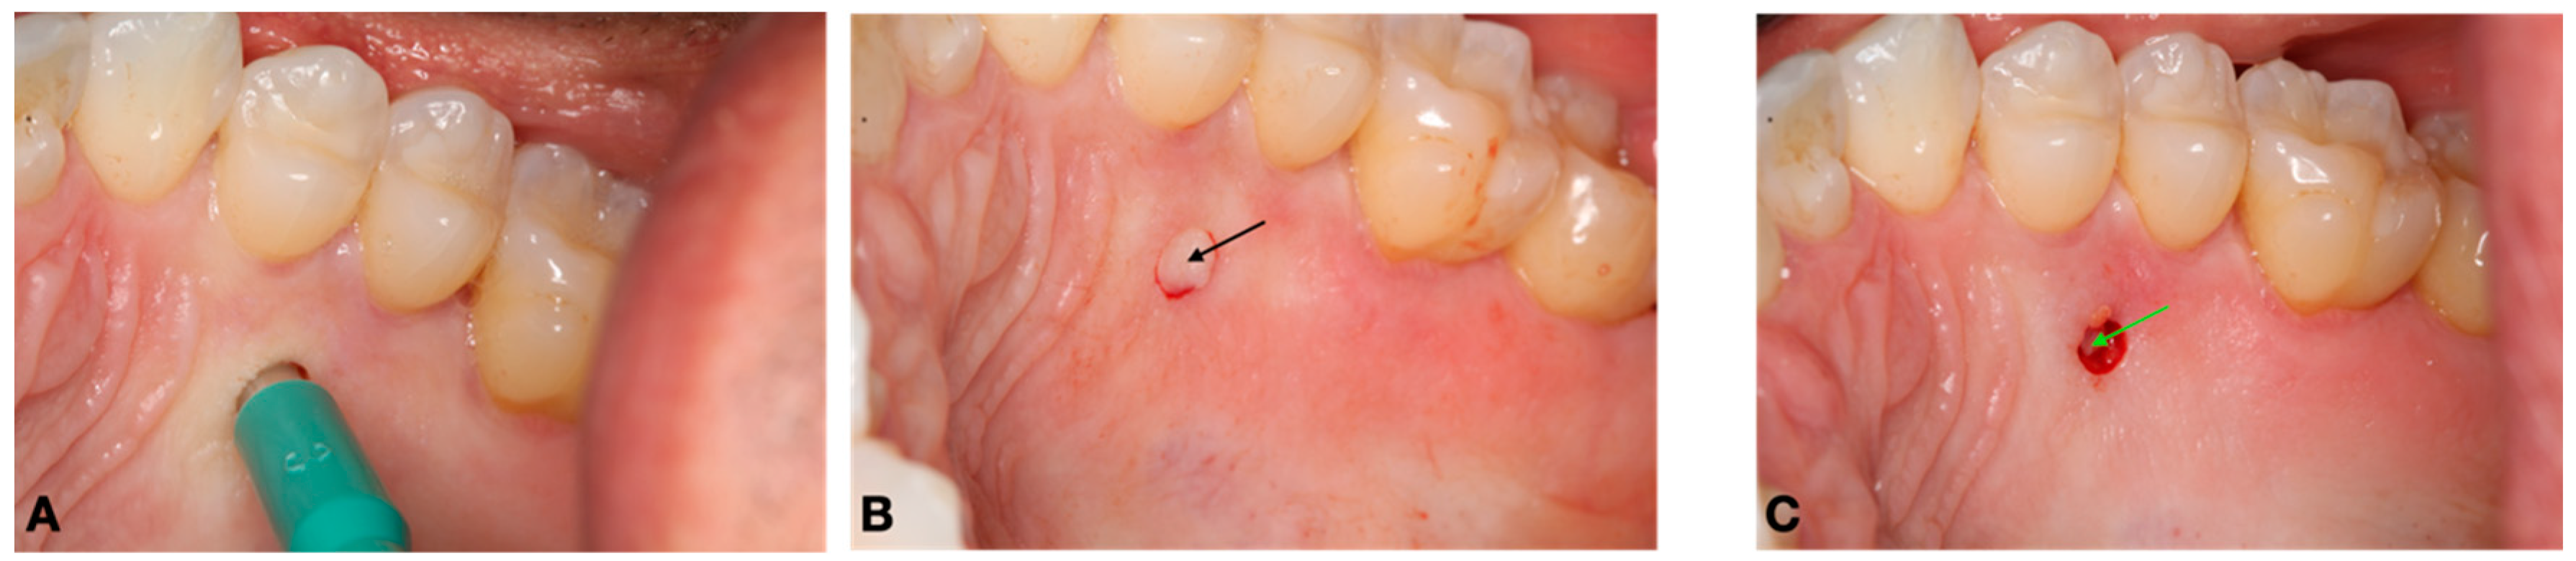

2.2. Surgical Procedure and Pre- and Postoperative Care